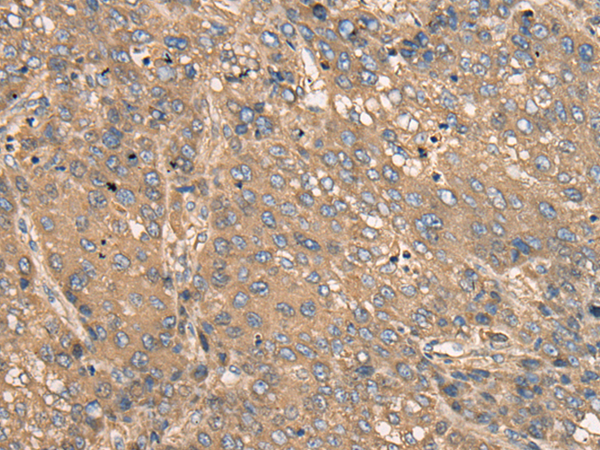

IHC positive control: |

Human liver cancer |

IHC Recommend dilution: |

25-100 |